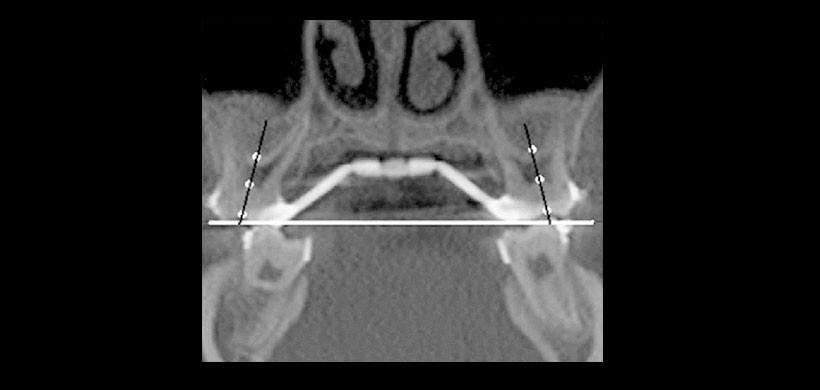

Figura 4: Tomografía cone beam. Postoperatorio, muestra la desmordida posterior a nivel de las primeras molares superiores.